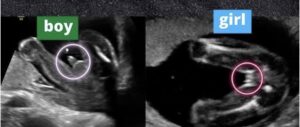

يستطيع الطبيب المساعدة على تحديد نوع الجنين بالبحث عن شكل اعضاء الجنين الذكر والتي تظهر في تصوير السونار بشكل غطاء السلحفاة وتسمى علامة السلحفاة turtle sign كما يتضح في الصورة التالية.

بينما تظهر اعضاء الاجنة الإناث في شكل ثلاثة خطوط متوازية ويسمى هذا الشكل علامة البرجر (كأن الثلاثة خطوط هم شطيرتي الخبز بينهما البرجر) كما يتضح في هذه الصورة.

وفيما يلي بعض صور السونار التي يمكن ان تساعدك على التفرقه بين الاجنة الذكور والاناث في تصوير السونار.